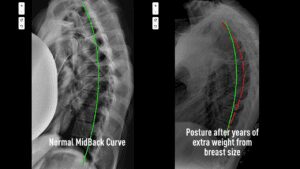

I see many female patients who have larger breasts. While society might focus on the visual aspect, as a doctor, I see the physics.

Extra weight on the front of the chest creates a constant downward pull. It acts like a fulcrum, pulling the upper back forward and rounding the shoulders. To compensate, the muscles between the shoulder blades have to work overtime, 24/7, just to keep the spine upright.

Many women deal with burning pain between the shoulder blades from their early teens. By the time they are adults, they are frustrated. I have seen breast reduction surgeries reach an all-time high because women are desperate for relief [3].

While surgery is a personal choice, it is often treated as the only solution. But often, the pain persists even after surgery because the structure of the spine has already changed. The curve has buckled. Removing the weight doesn’t automatically fix the 20 years of spinal shifting that occurred beforehand.

If you are the woman with the heavy chest, we work on strengthening the posterior chain (the back muscles) and correcting the thoracic curve (kyphosis) so your spine acts like a strong column that can support the weight effortlessly, rather than a bending willow branch that is about to snap.